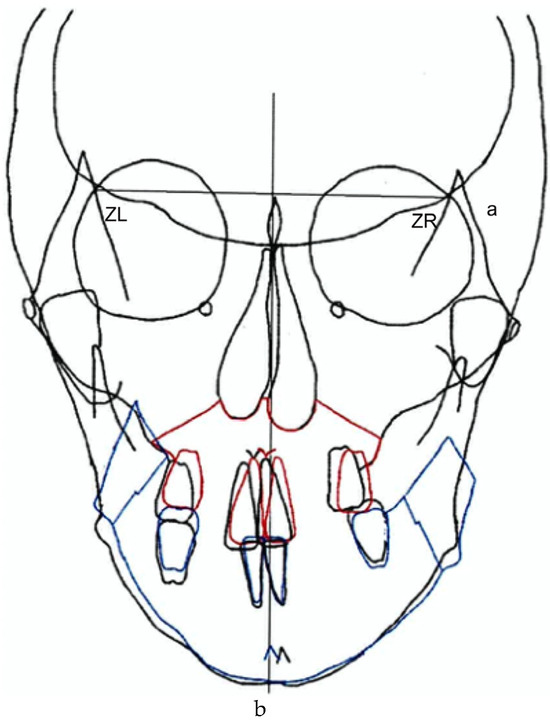

Consequently, since the maxilla is highly deformed, rolling and translation were performed to align the maxillary midline with the facial midline. However, the mandible was rolled, translated, and set back to improve the deformity and lateral symptoms. The goal was to improve the morphology (Figure 4).

Figure 4.

Pre-treatment record. Frontal prediction. (a) ZL–ZR plane. (b) Midline. Jaw surgery prediction. Red line: Intraoperative prediction of the maxilla. Blue line: Intraoperative prediction of mandible.